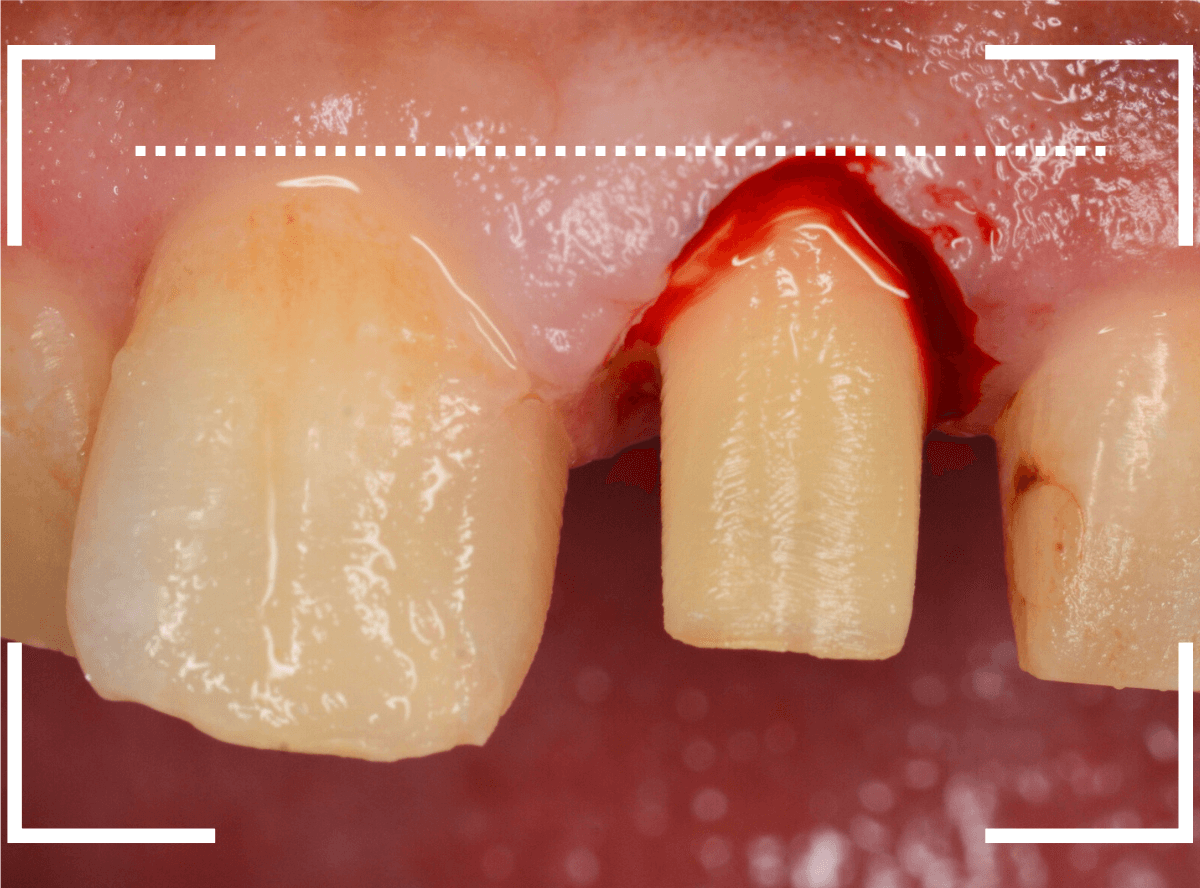

治療をするためには、歯肉の形をトリミングするなどの若干の外科処置が必要です。

多少の痛みを伴いますが「頑張ります!」との事でしたので、そこも含めて治療する事になりました。

次に、隣の歯との高さに揃えるために、歯肉をメスで切開して、そこに合わせて歯の形を形成しなおします。

この形に合わせた仮歯を製作し、歯肉が落ち着くまでしばらく経過観察します。